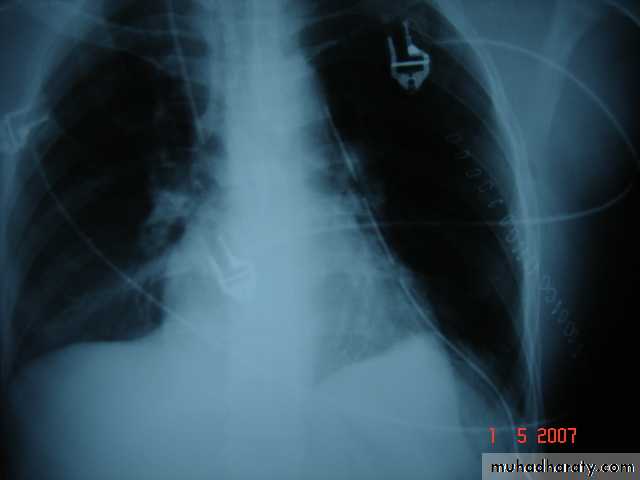

• 6-Great vessels injuriesInjuries to the thoracic aorta and its branches can occur mainly with deceleration injury . Most patients with ruptured aorta die immediately but in 10% of patients the per aortic tissues and pleura are able to maintain the intravascular pressure producing false aneurysms ,which can be diagnose by CT angiography and needs immediate surgery .

Traumatic aortic disruption is a time-sensitive injury requiring rapid and accurate diagnosis to prevent death.

Widen mediasinum

Descending aortic injuryEndo vascular stent control